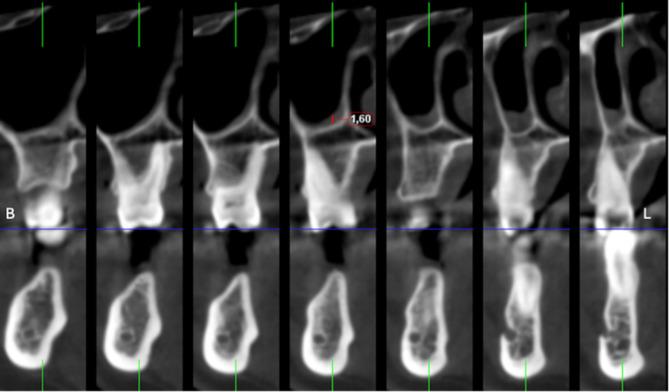

Nine hundred thirty-nine maxillary posterior segment images from 527 subjects were retrospectively scanned via CBCT. A total of 826 premolar, 701 first molar and 817 s molar teeth were examined. The maxillary sinuses in each segment were divided into anterior, median and posterior regions according to the tooth roots they were associated with, and their membrane thicknesses were measured and categorized. The effects of age and gender on membrane thickness were evaluated. T tests and one-way ANOVA were used to analyze differences between groups, followed by post hoc Tukey tests for multiple comparisons. Additionally, correlation analyses were performed to investigate the relationships between the categorized membrane thicknesses and periodontal bone loss.

回顾性扫描了来自527名受试者的939张上颌后段图像。共检查了826颗前磨牙、701颗第一磨牙和817颗第二磨牙。每个节段的上颌窦根据与其相关的牙根分为前部、中部和后部区域,并测量其膜厚度并进行分类。评估年龄和性别对膜厚度的影响。使用t检验和单因素方差分析来分析组间差异,随后进行事后Tukey检验以进行多重比较。此外,进行相关性分析以研究分类后的膜厚度与牙周骨丧失之间的关系。